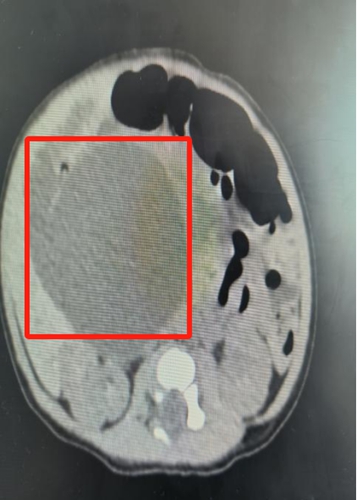

安安出生后,新生兒外科、NICU、新生兒內(nèi)科、產(chǎn)科等科室再次進行MDT會診,進行了全面評估,檢查結(jié)果顯示:膽總管囊腫,3*3cm。

△安安的囊腫迅速長到6*5cm,小小的身體里埋著一個雞蛋大小的“炸彈”。

救治團隊邊控制黃疸病情,穩(wěn)住肝功能,邊根據(jù)預案密切觀察,發(fā)現(xiàn)寶寶的囊腫在短時間內(nèi)迅速增大,7天內(nèi)從最初的3*3cm增長到6*5cm。